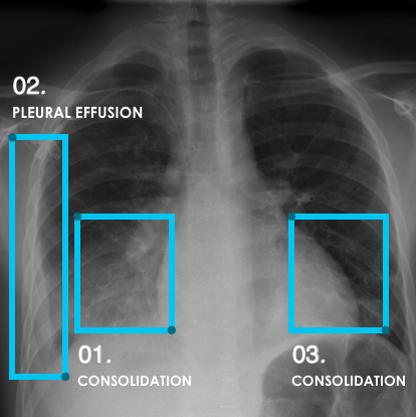

A 76-year-old male presented with chest pain and dyspnoea. Patchy infiltrates in the right and left upper zones with air space opacification noted in the right midzone and left lower zone. RADIFY® has detected the lesions with bounding boxes in the region of interest. Result: High probability of pneumonia